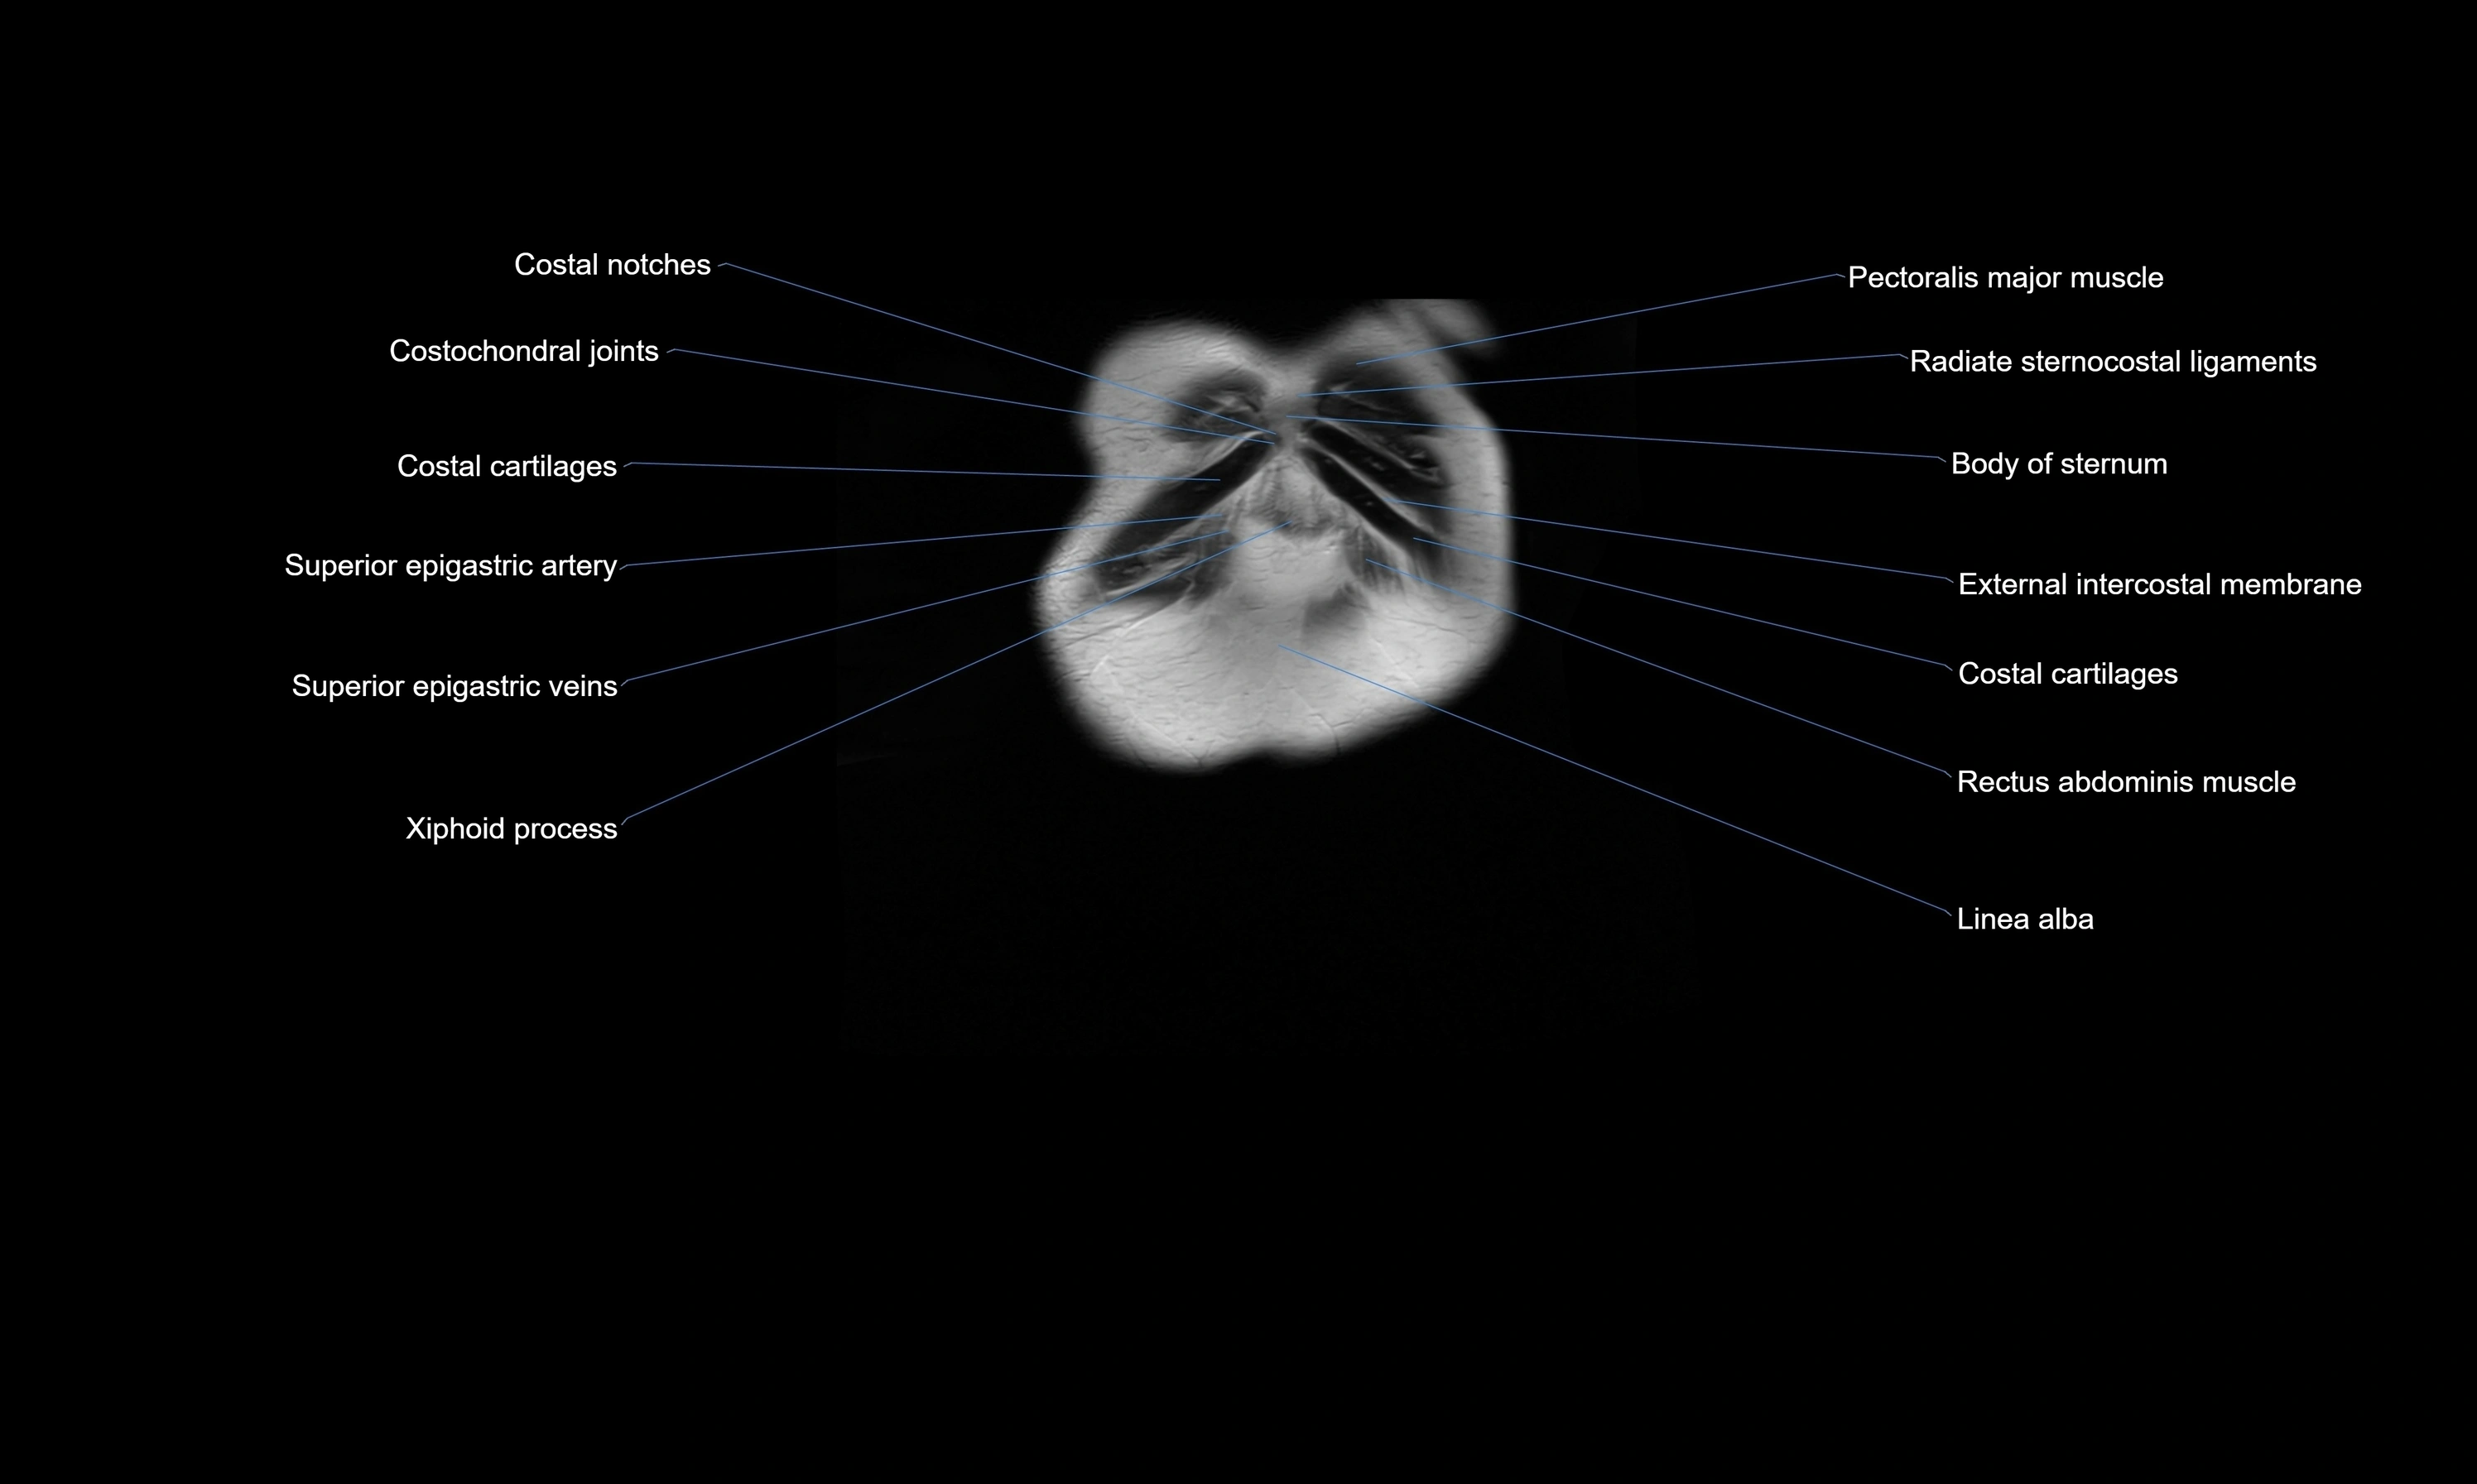

- Costochondral joints

- Superior epigastric artery

- Superior epigastric veins

- Transversus thoracis muscle

- Rectus abdominis muscle

- Linea alba